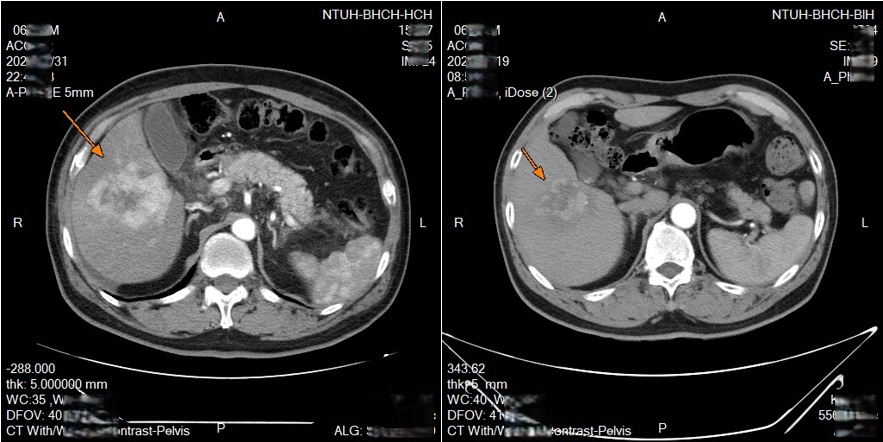

新竹臺大分院收治一名63歲男性,先是得了淋巴癌,而後在治療期間又發現肝腫瘤,確診肝癌。經醫療團隊與病人充分討論後,安排進行鎖骨下導管置放於肝動脈灌注化療,歷經兩次療程腫瘤明顯縮小。

透過可移動式的導管放置,每次治療後都可以重新調整導管的位置,若導管移位或堵塞,可以迅速處理,從而達到更好的治療效果,並且減少併發症的發生。臨床上,不少病人對治療產生良好反應,部分病人在影像追蹤中可見腫瘤縮小或消失,顯示治療具相當潛力。